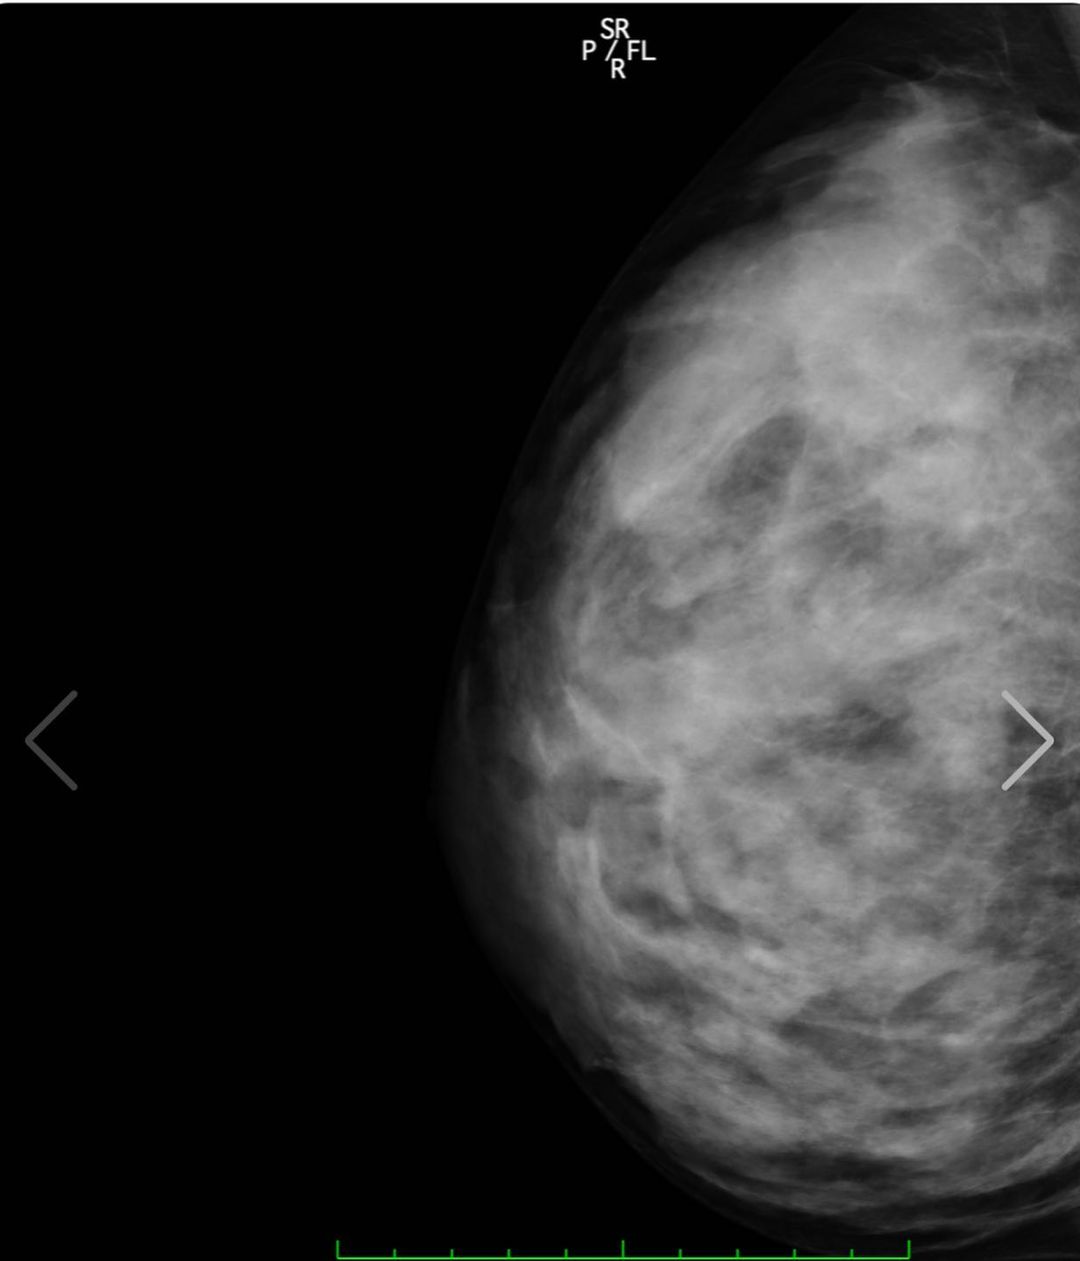

写真は私の胸部レントゲンです!www

裸を通り越して私の骨と脂肪を

見れたあなたには幸運が訪れると

信じてます❤️(私の胸は遺伝です)w